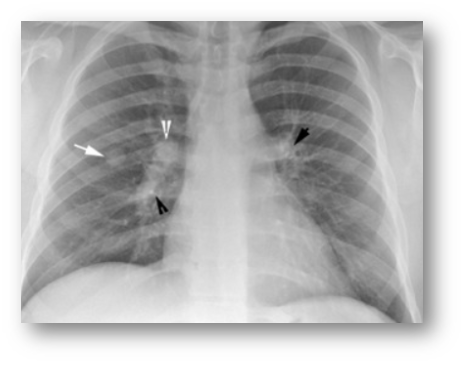

폐결절 CT 검사 방법

폐결절을 정확히 진단하기 위해서는 CT 검사가 필수적이에요. 저선량 흉부 CT는 방사선 노출을 최소화하면서도 결절을 발견할 수 있어요. 특히 정기 검진이나 추적 관찰에 많이 사용된답니다.

필요에 따라 조영제를 사용하는 CT 검사도 있어요. 조영제를 사용하면 결절의 혈류나 조직 특성을 더 자세히 알 수 있어요. 하지만 조영제 알레르기가 있는 분들은 주의해야 해요.